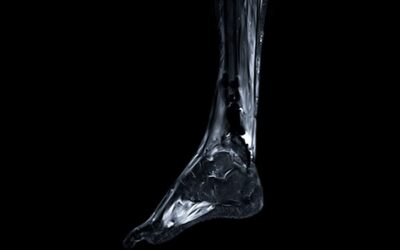

Pied | Cheville | Tendon d’achille

Les pathologies du pied et de la cheville

La cheville

Les Drs Baudrier et Shitrit diagnostiquent et prennent en charge l’ensemble des pathologies de la cheville, de l’instabilité à l’arthrose.

Le talon d’Achille

Les Drs Baudrier et Shitrit diagnostiquent et prennent en charge l’ensemble des pathologies du tendon d’achille de la rupture jusqu’au transfert tendineux.